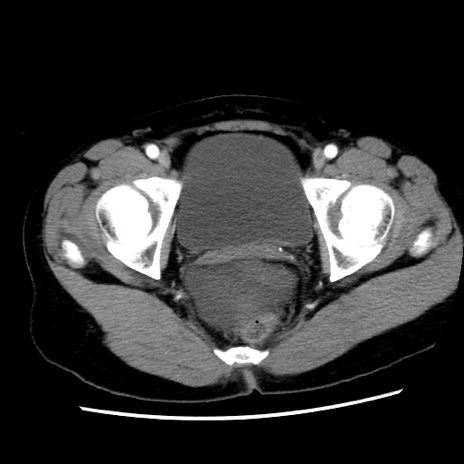

症例10(横断像)

【症例】 50歳代女性

【主訴】 腹痛

【現病歴】前日生レバーを食べた。今朝に排便あり。 昼前に突然発症の腹痛を生じ、当院救急外来を受診した。

【既往歴】 子宮筋腫にてで子宮全摘後

【身体所見】 意識清明、腹部:平坦、軟、下腹部やや左を中心に圧痛・反跳痛あり、筋性防御あり

【データ】WBC 7800、CRP 0.07